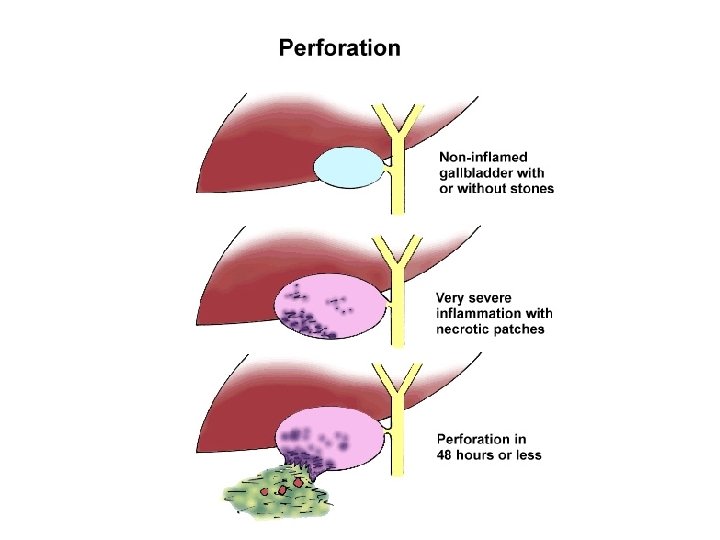

• KOMPLIKACIONET: - Kolecistit i supuruar (empiem i kolecistes) Perforim i kolecistes Pankreatit Kolangit Sepsis